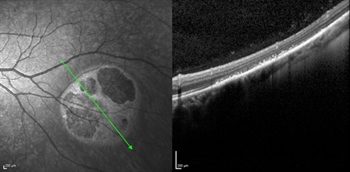

The dilated funduscopic exam revealed an approximately 5 x 5 mm heavily pigmented choroidal lesion inferotemporal from the fovea and optic nerve (Figure 1). The lesion was flat without subretinal fluid or orange pigment. The cup-to-disc ratio, macula, and vessels were otherwise normal. Optical coherence tomography (OCT) showed atrophy of the overlying outer retinal layers and thickening of the retinal pigment epithelium (RPE) with thinning of the choroid underlying the lesion (Figure 2).

| Figure 1 | Figure 2 |